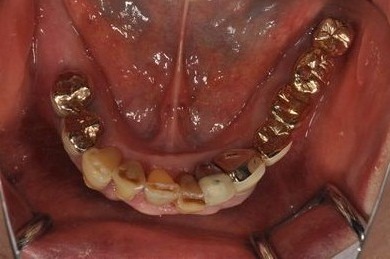

抜歯即日スピードインプラント治療+インプラント除去+セラミック治療

| 性別/年齢 | 女性 / 76歳 | ||||||||||||||||||||||||||||||||

| 主訴 | 20年前に入れたインプラントの周囲が腫れて気になっている。左下の一部治療後の歯が欠けている。 | ||||||||||||||||||||||||||||||||

| 治療内容 | インプラント5本(抜歯即日スピードインプラント)、ハイブリッドセラミック9本(セラミック用土台2本)、メタルボンドセラミック2本(メタルボンド用土台1本)、インプラント除去1本 | ||||||||||||||||||||||||||||||||

| 総治療費 | 2,514,645円 | ||||||||||||||||||||||||||||||||

| 治療期間 | 1年11ヶ月 |